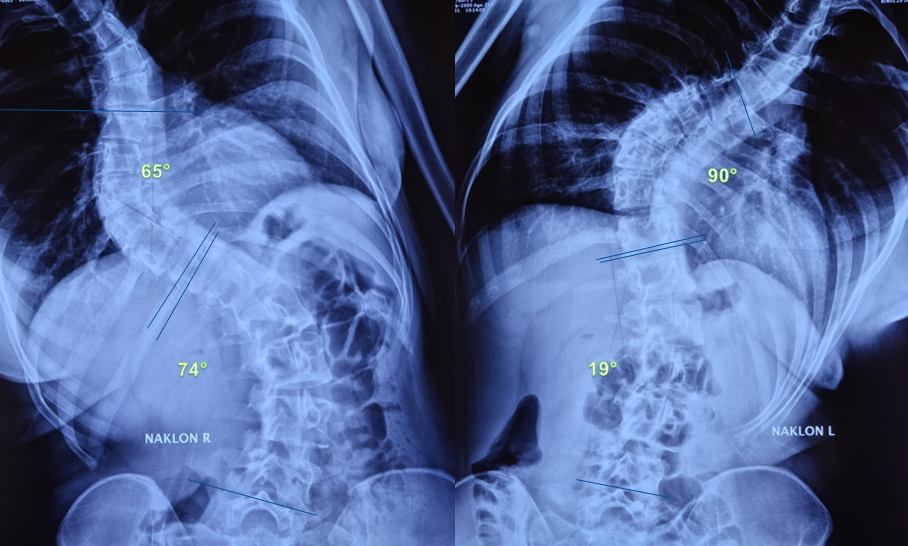

Степень искривления позвоночника определяют на основании результатов рентгена позвоночника. Существует несколько методик ее установления, но все они сводятся к выполнению несложных геометрических построений на полученных снимках. Предварительно врач обязательно оценивает форму, положение, размеры и особенности каждого позвонка, чтобы выявить причину искривления позвоночного столба. Также оценке подвергается глубина ротации (поворота) позвонков.

Сколиоз позвоночника 3 степени диагностируют при угле искривления в пределах 25—50°. Характер внешних проявлений зависит от того, какие отделы позвоночника поражены больше всего. Поэтому в таких случаях может наблюдаться: